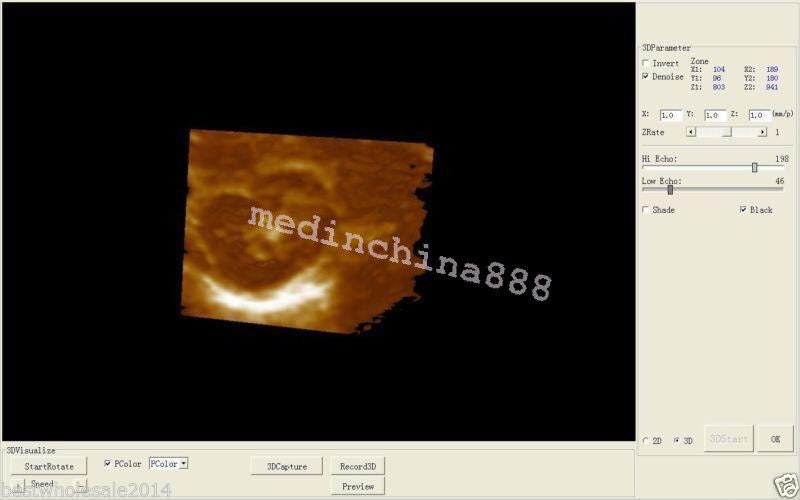

Image mode: B, B+B, 4B, B+M, M